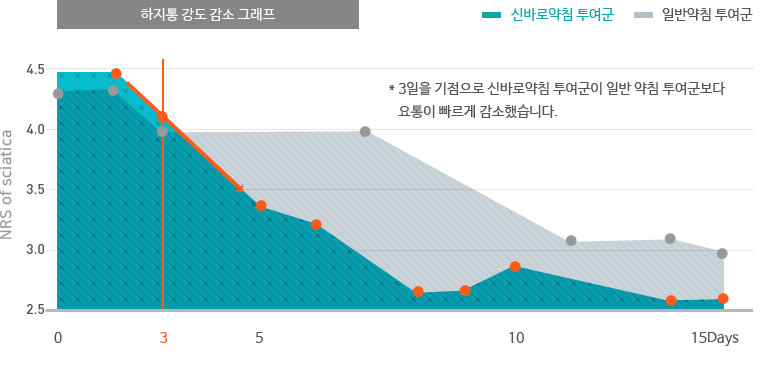

일반 약침보다 빠른 통증 감소 효과

자생척추관절연구소에서 디스크 환자를 대상으로 신바로약침과 일반약침의 효능을 비교한 임상연구 결과, 신바로약침

이 일반약침보다 척추디스크로 인한 허리통증과 다리통증을 더 빠르게 감소시키는 것으로 나타났습니다.

이 일반약침보다 척추디스크로 인한 허리통증과 다리통증을 더 빠르게 감소시키는 것으로 나타났습니다.

- 연구기관 : 자생한방병원

- 저널명 : 척추신경추나의학회지 2011;6(2):109-119

- 논문명 : 요추추간판탈출증에 대한 신바로약침의 효과 : 무작위 대조군 시험